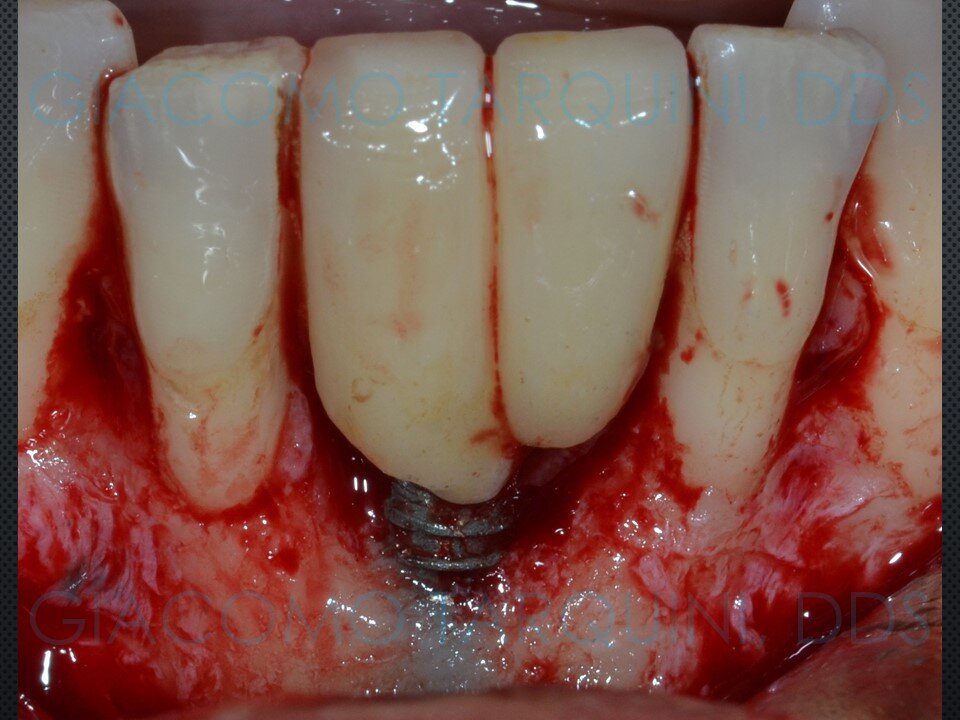

Viene presentato un caso di rigenerazione ossea guidata attorno a un impianto che aveva perso parte del suo supporto osseo a causa di una pregressa peri-implantite. Le spire esposte vengono decontaminate sfruttando le note proprietà della cavitazione ultrasonica per mezzo del dispositivo “Piezoclean by Dr. Giacomo Tarquini”, mentre la fase rigenerativa viene effettuata secondo il protocollo denominato “Poncho technique”. Questo approccio consente una ricostruzione prevedibile del tessuto osseo senza dover necessariamente rimuovere l'abutment e la protesi al fine di ottenere una guarigione sommersa.

In casi selezionati, questa tecnica permette di mantenere estetica e funzione della riabilitazione protesica su impianti, riducendo al contempo sia l’invasività dell’intervento sia i tempi complessivi della riabilitazione, poiché elimina completamente la necessità di rimuovere e successivamente reinserire sia la corona protesica sia l’abutment.

CASO CLINICO: